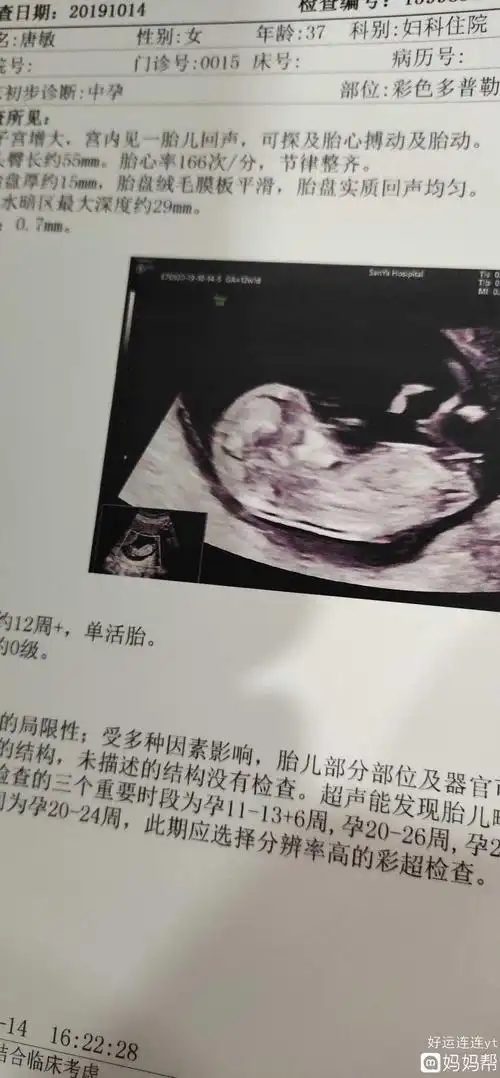

查nt单数据三个亮点是男孩女孩,nt单主要看什么有什么用